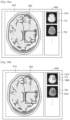

- FIG. 7A illustrates a plurality of MR images reconstructed by scanning an object according to different protocols.

- An MRI protocol is a protocol related to a pulse sequence of an MR signal.

- examples of the protocol include a protocol for obtaining a T1-weighted image (hereinafter, referred to as a T1W protocol), a protocol for obtaining a T2-weighted image (hereinafter, referred to as a T2W protocol), a protocol for obtaining a T1 flair image (hereinafter, referred to as a T1W flair protocol), a protocol for obtaining a T2 flair image (hereinafter, referred to as a T2W flair protocol), a protocol for obtaining a diffusion image (hereinafter, referred to as a diffusion protocol), and a protocol for obtaining a perfusion image (hereinafter, referred to as a perfusion protocol).

- Examples of information that is post-processed or calculated by using image data obtained by applying a protocol include a cerebral blood volume (CBV) map, a cerebral blood flow (CBF) map, histogram equalization information, an apparent diffusion coefficient (ADC) map, a trace map, a perfusion map, an fMRI map showing brain functions, an MRI property map, such as a T1 map or a T2 map, a fractional anisotropy map, and a diffusion tractography map.

- An image reconstructed by using image data obtained by applying a T1W protocol is referred to as a T1-weighted image

- an image reconstructed by using image data obtained by applying a T2W protocol is referred to as a T2-weighted image

- An image reconstructed by using image data obtained by applying a T1W flair protocol is referred to as a T1W flair image

- an image reconstructed by using image data obtained by applying a T2W flair protocol is referred to as a T2W flair image.

- An image reconstructed by using image data obtained by applying a diffusion protocol is referred to as a diffusion image

- an image reconstructed by using image data obtained by applying a perfusion protocol is referred to as a perfusion image.